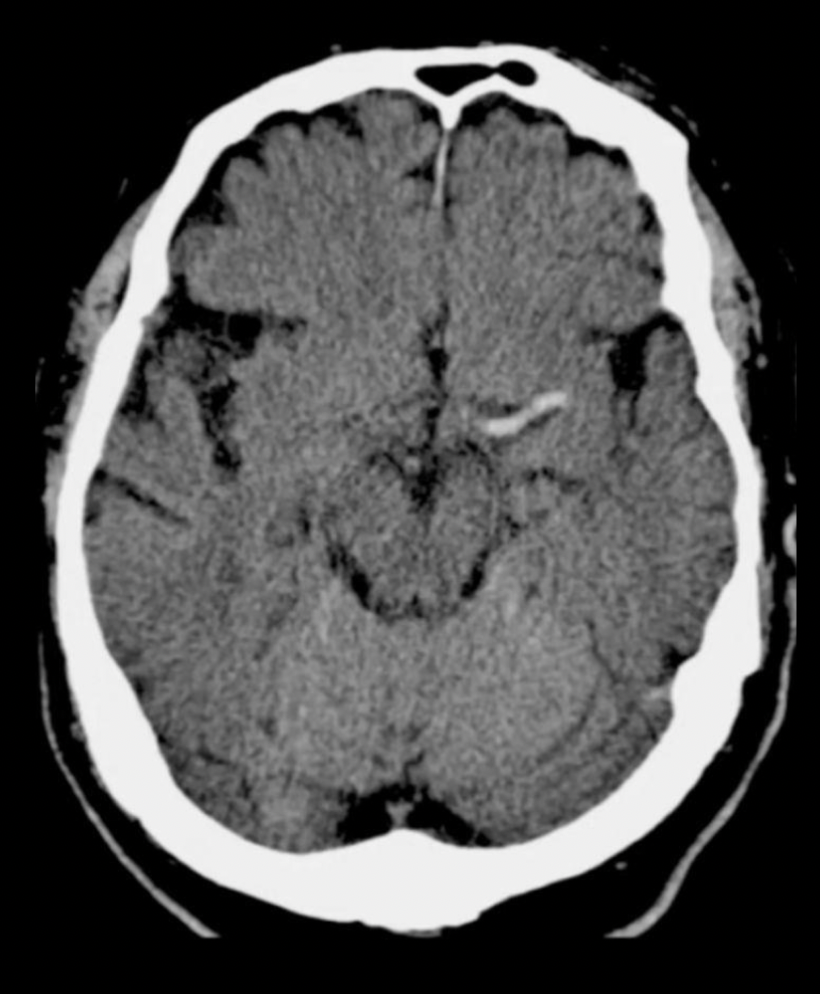

20

Q

Diagnóstico

A

EVC isquémicoen fase crónica